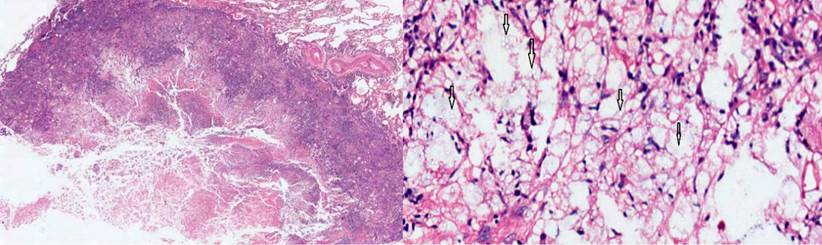

Ante la sospecha de un tuberculoma, se realizó una biopsia en cuña del nódulo del lóbulo inferior, con una patología que reportó un parénquima pulmonar con enfermedad granulomatosa crónica caseificante, compatible con criptococosis, y negativo para bacilos acidorresistentes (BAAR) (Figura 3). Los cultivos de hongos confirmaron un moderado crecimiento de Cryptococcus neoformans, mientras que la PPD negativa descartó la tuberculosis latente.

Los medios diagnósticos considerados más específicos son el cultivo y la biopsia del tejido; esta última es la más importante y se puede obtener por punción o quirúrgicamente. Las coloraciones empleadas son las de tinta china, Gomory, ácido peryódico de Schiff (Periodic Acid-Schiff, PAS) y mucicarmina 12. En el caso de nuestro paciente, se realizaron cultivo y biopsia, que demostraron la presencia de las esporas del criptococo.